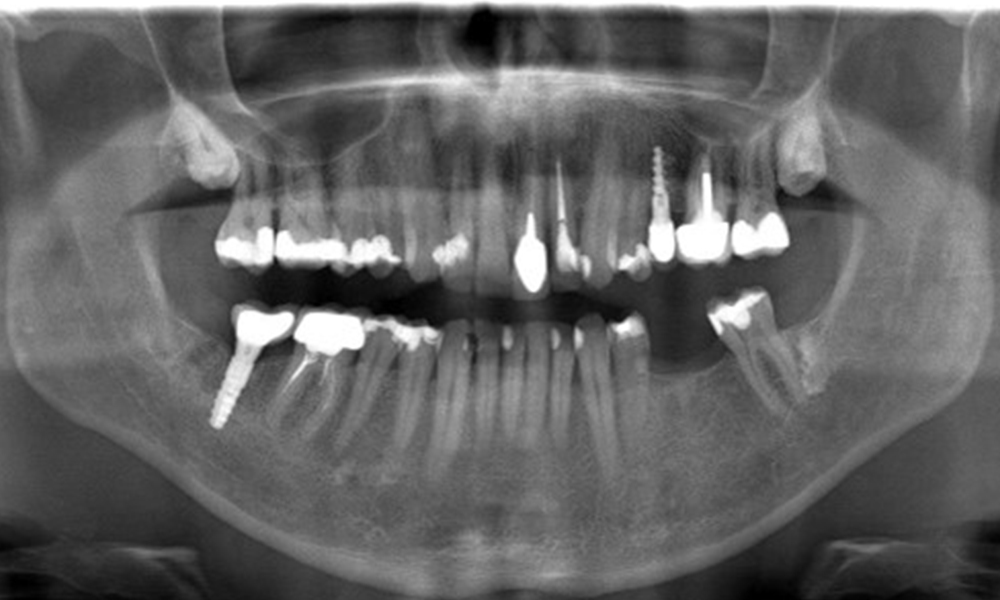

Рентгеновата снимка показва загуба на кост

OPG: 29/02/2024

Рентгенова снимка (или рентгенова снимка на захапката)

Рентгенова снимка (или рентгенова снимка на захапката), заснета на: 18/02/2021